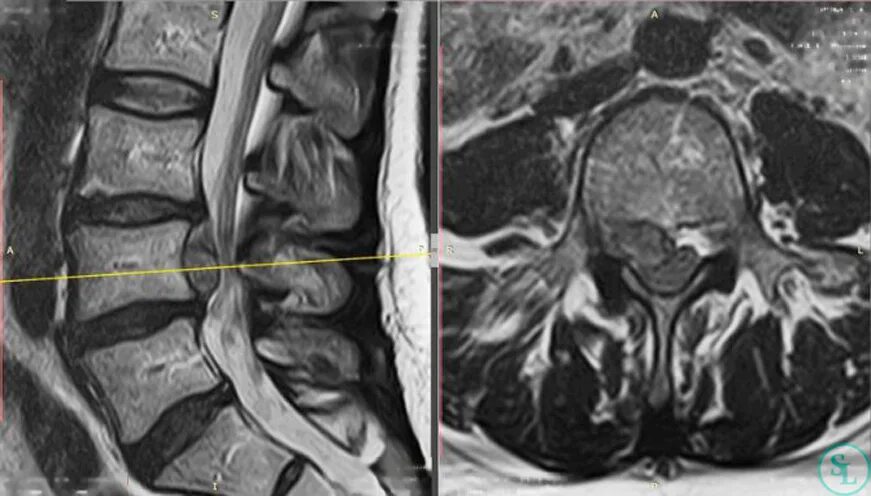

На мрт нужно снимать